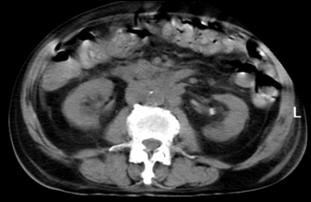

4.3. Tomografia computerizata si rezonanta magnetica nucleara

Informatiile furnizate de aceste metode moderne imagistice ridica procentajul acuratetei diagnostice pana la 85% in aprecierea infiltratiei parietovezicale a tumorilor (T) si la circa 90% pentru decelarea adenopatiei pelviene.

Figura 37. Aspect

tomografic de tumora vezicala. Formatiune tumorala

exofitica protruziva intravezical situata pe peretele

postero-lateral stang. Figura 38. CT pelvin - Tumora voluminoasa in hemivezica

dreapta Figura 39. CT abdominal - Adenopatie extraregionala

periaortico-cava

a. b. Figura 40. Aspect CT - Metastaza

hepatica dintr-o tumora vezicala.

Figura 41. a,b) Aspect CT - Metastaza

vertebrala si costala dreapta